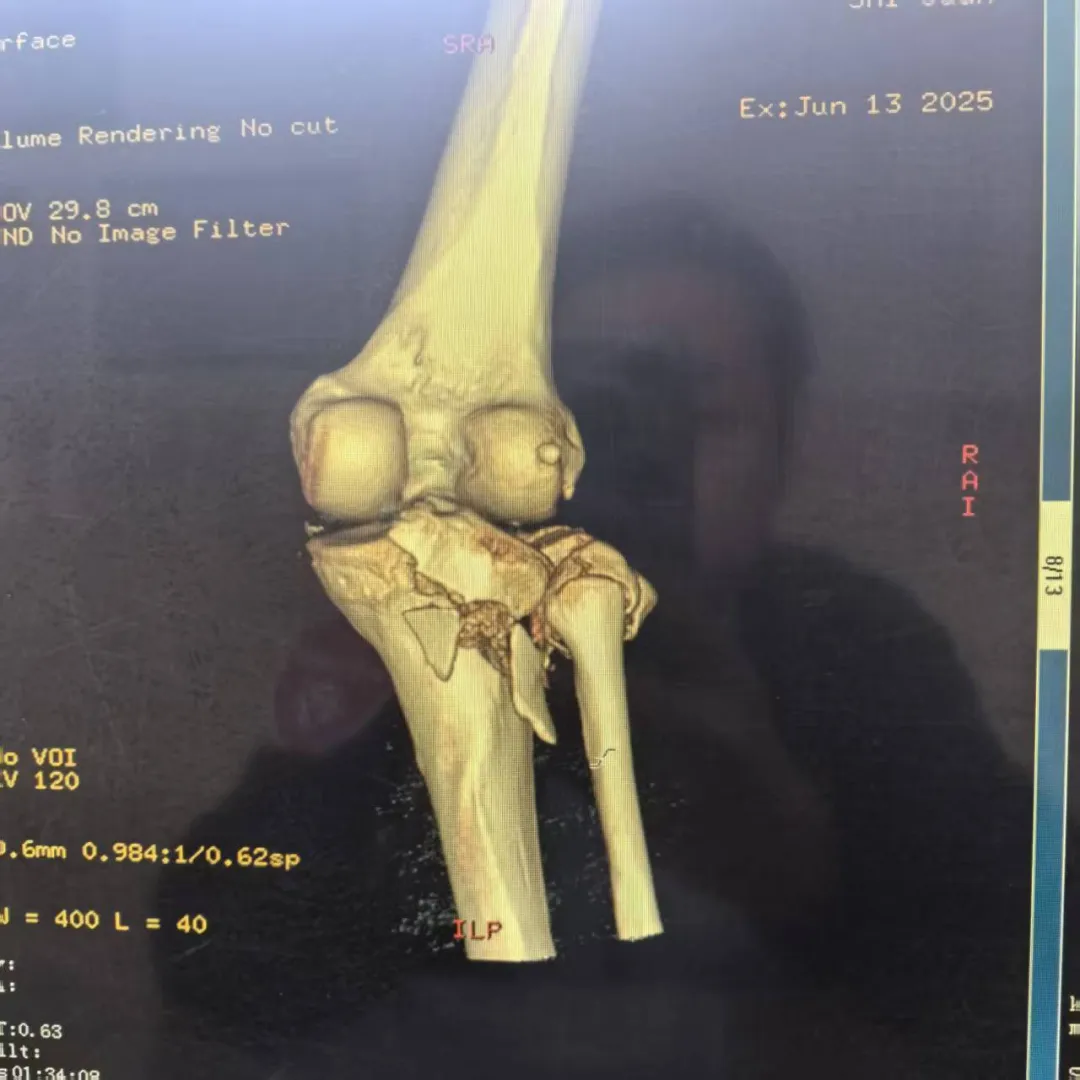

病例难点:直面手术挑战

患者石女士,34岁,因高处坠落导致右膝严重损伤。经过详细的影像学检查,诊断确认:胫骨平台后外侧粉碎性骨折(Schatzker Ⅱ型)、膝关节前、后交叉韧带及内外侧副韧带损伤、外侧半月板后角Ⅲ度损伤,内侧半月板后角Ⅰ度损伤。

骨折块粉碎严重,复位固定难度极大

面对这一复杂病例,科室医疗团队组织全科进行术前讨论,结合最新版《胫骨平台骨折诊断与治疗专家共识》,经过精密规划,最终决定采用改良Frosch后外侧入路这一先进术式。